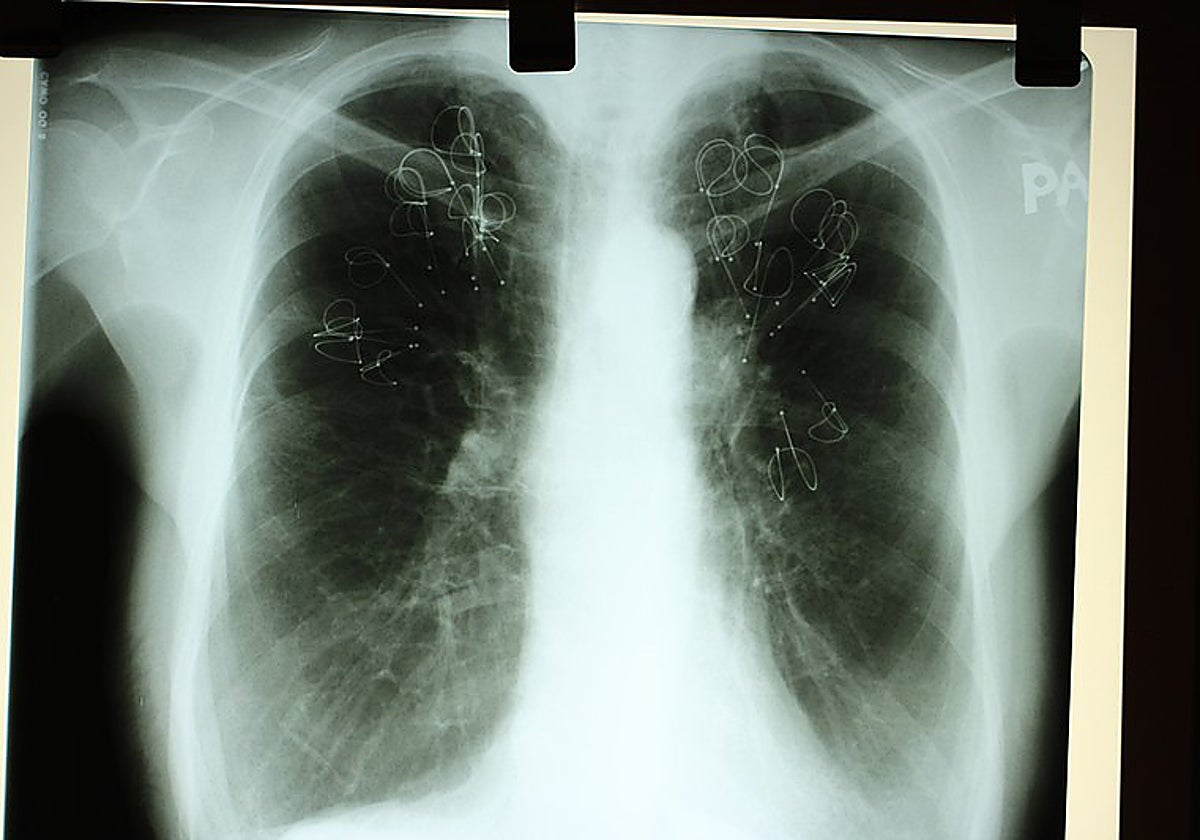

El cáncer es la segunda causa de muerte en nuestro país, por detrás de las enfermedades del sistema cardiovascular. Los cánceres más mortales siguen siendo el de pulmón (18,2% del total de muertes por cáncer), el colorrectal, el hepático, el de estómago y el de mama (6,9%).

Los expertos llevan ya un tiempo preocupados por el aumento en el cáncer de pulmón en mujeres, con una tasa de incidencia en 2023 que casi triplica la de 2001. El consumo de tabaco continúa siendo superior en hombres que en mujeres y por lo tanto también la incidencia de este tipo de cánceres, pero es muy probable que en las mujeres siga incrementándose en los próximos años.